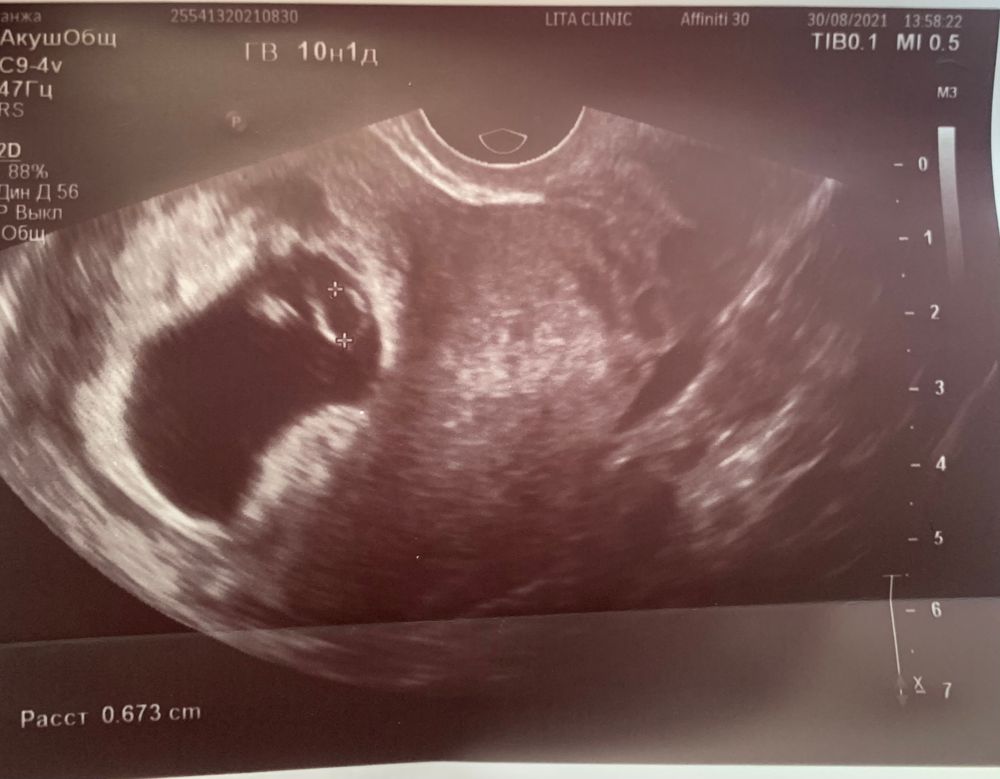

10 недель УЗИ. Мысли о скрининге и нипт.

Добра мира и любви, потому что его максимальный размер в источниках - 6 мм... тем более с 8 10 неделю он должен уменьшаться, а у меня наоборот вырос.. а к 12 недели исчезнуть